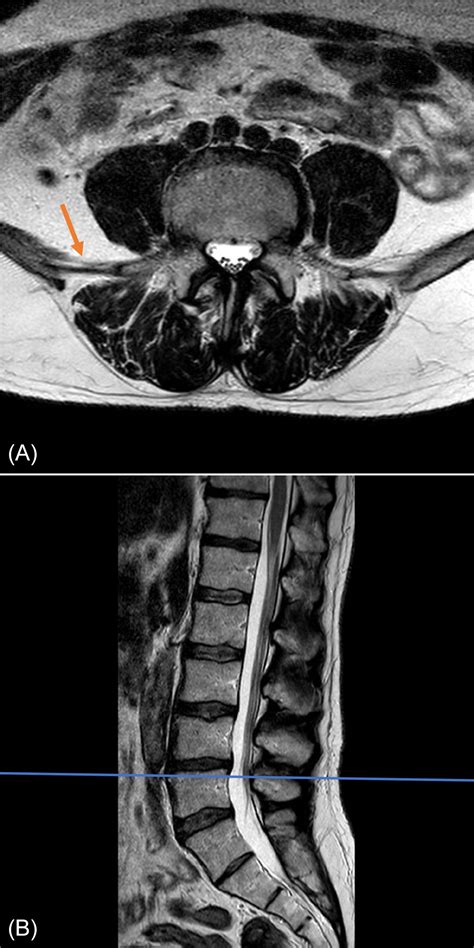

The lumbar spine is the lower section of your back, consisting of five vertebrae (labeled L1 through L5). This region supports the majority of your body weight and facilitates movement, making it highly susceptible to wear and tear, injury, and structural issues. A lumbar spine MRI uses strong magnetic fields and radio waves to create high-resolution images of the bones, intervertebral discs, spinal cord, nerve roots, and surrounding soft tissues.

Unlike an X-ray or CT scan, which are excellent for viewing bone density and fractures, an MRI excels at highlighting soft tissue abnormalities. It can detect subtle changes in disc hydration, identify inflammation, and reveal precisely where nerves may be compressed by bulging or herniated discs.

Once the scan is complete, the images are sent to a radiologist, a physician who specializes in interpreting diagnostic imaging. They will prepare a report detailing their findings and send it to the doctor who ordered the test. It is common to see medical terminology in these reports, such as "annular tear," "facet hypertrophy," or "neural foraminal narrowing."

It is important not to panic if you read words that sound alarming. Many age-related changes, such as mild disc bulging or minor arthritis, are commonly found even in people who have no back pain. Your physician will correlate the findings of the lumbar spine MRI with your physical symptoms and clinical examination to determine the most effective treatment plan, which may range from physical therapy and epidural steroid injections to surgical intervention.

- lumbar spine mri images

- lumbar spine mri anatomy